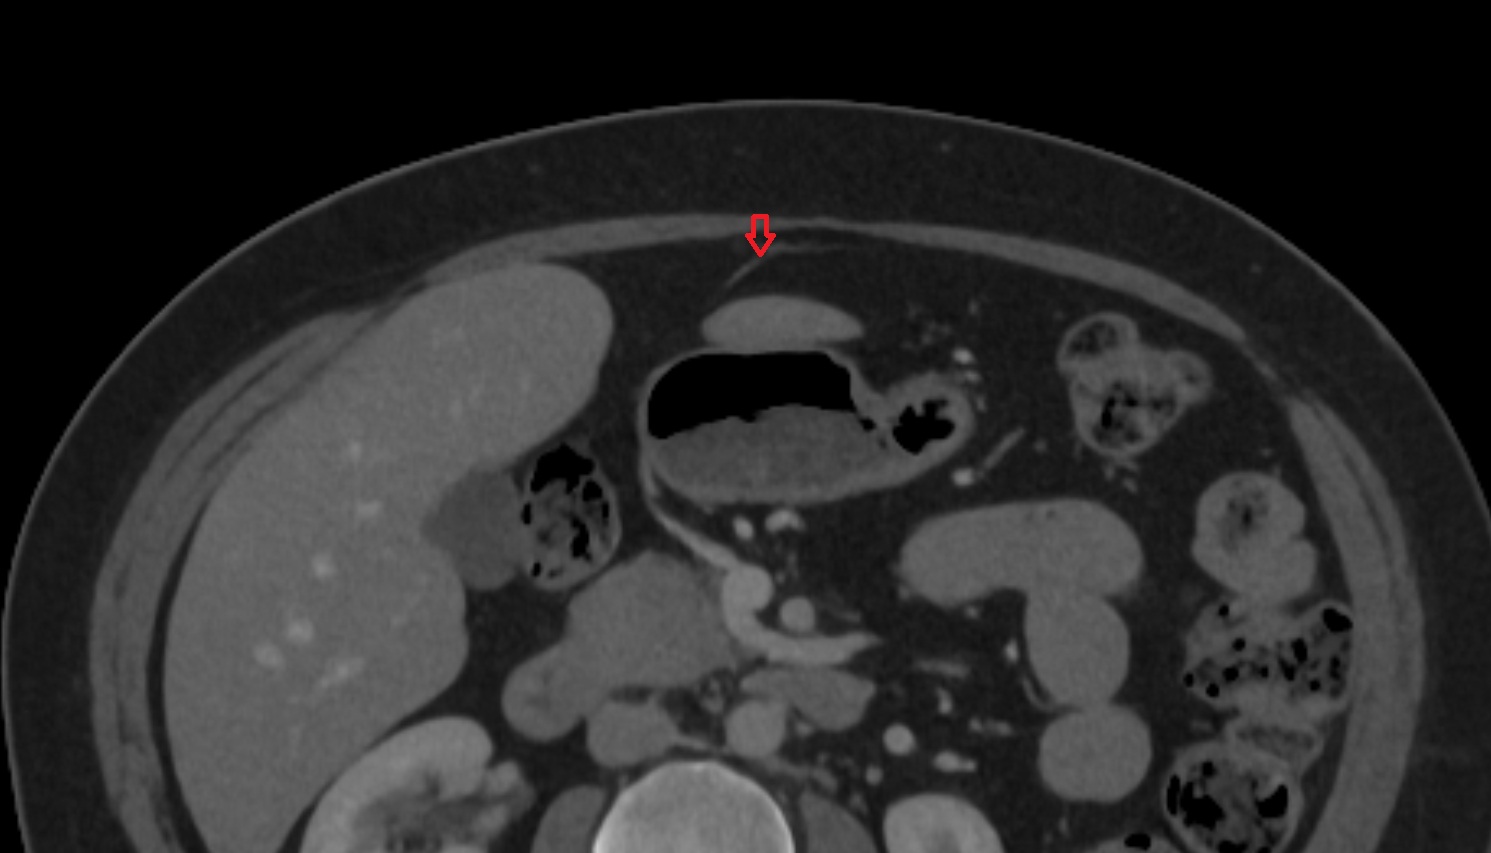

- kidneys

- Right kidney

- Left kidney

- Kidney cortex (Renal cortex)

- Renal medulla

- Renal pyramids

- Renal artery

- Renal vein